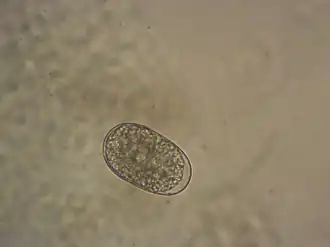

| Ei | |||||||||||||

De rondworm heeft twee dorsale en twee ventrale snijplaten rond de voorste rand van de mondholte. Verder heeft de rondworm een paar subdorsale en een paar subventrale tanden dicht bij de achterkant. De mannetjes zijn 7–9 mm lang en de vrouwtjes 9–11 mm lang. De levensduur is 3-5 jaar. Het vrouwtje kan 5.000 tot 10.000 eieren per dag produceren.[8] De dunwandige, ovale eieren zijn 56–74 μm lang en 36–40 μm breed.